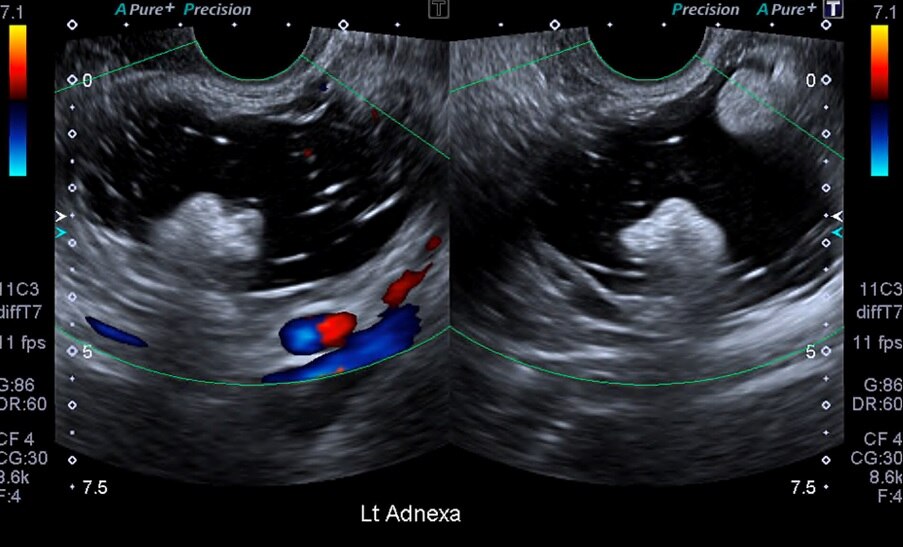

Figure 1(a,b). Ultasonographic picture of the case showing ovarian cyst Ovarian Cyst Journal Incidentally discovered ovarian cysts are common and most are benign, but a minority can represent ovarian cancer, which is. Up to 10% of women will have surgery for an ovarian cyst in their. Benign ovarian cysts are a common gynaecological presentation. The tvu screening examination is considered positive (abnormal and suspicious for ovarian cancer) when findings included: Adnexal masses or. Ovarian Cyst Journal.